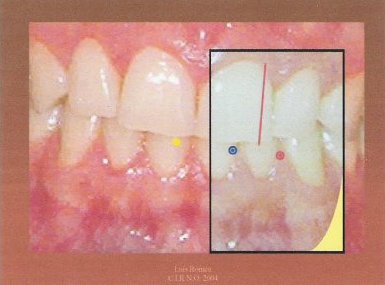

2.- Adherimos un trozo de papel celo a los incisivos superiores.

3.- Trazamos una línea con el rotulador sobre el papel celo de tal manera que comienza en el punto que marcamos en el primer paso, visto por transparencia, y asciende paralelo a la línea media facial del paciente. Este paso debe realizarse con mucho cuidado pues de él depende el éxito del procedimiento.

4.- Invitamos al paciente a realizar una lateralidad derecha. Es aconsejable que sea lo más amplia posible siempre y cuando el trayecto sea rectilíneo. Marcamos sobre el papel celo un punto encima del que pintamos en el primer paso.